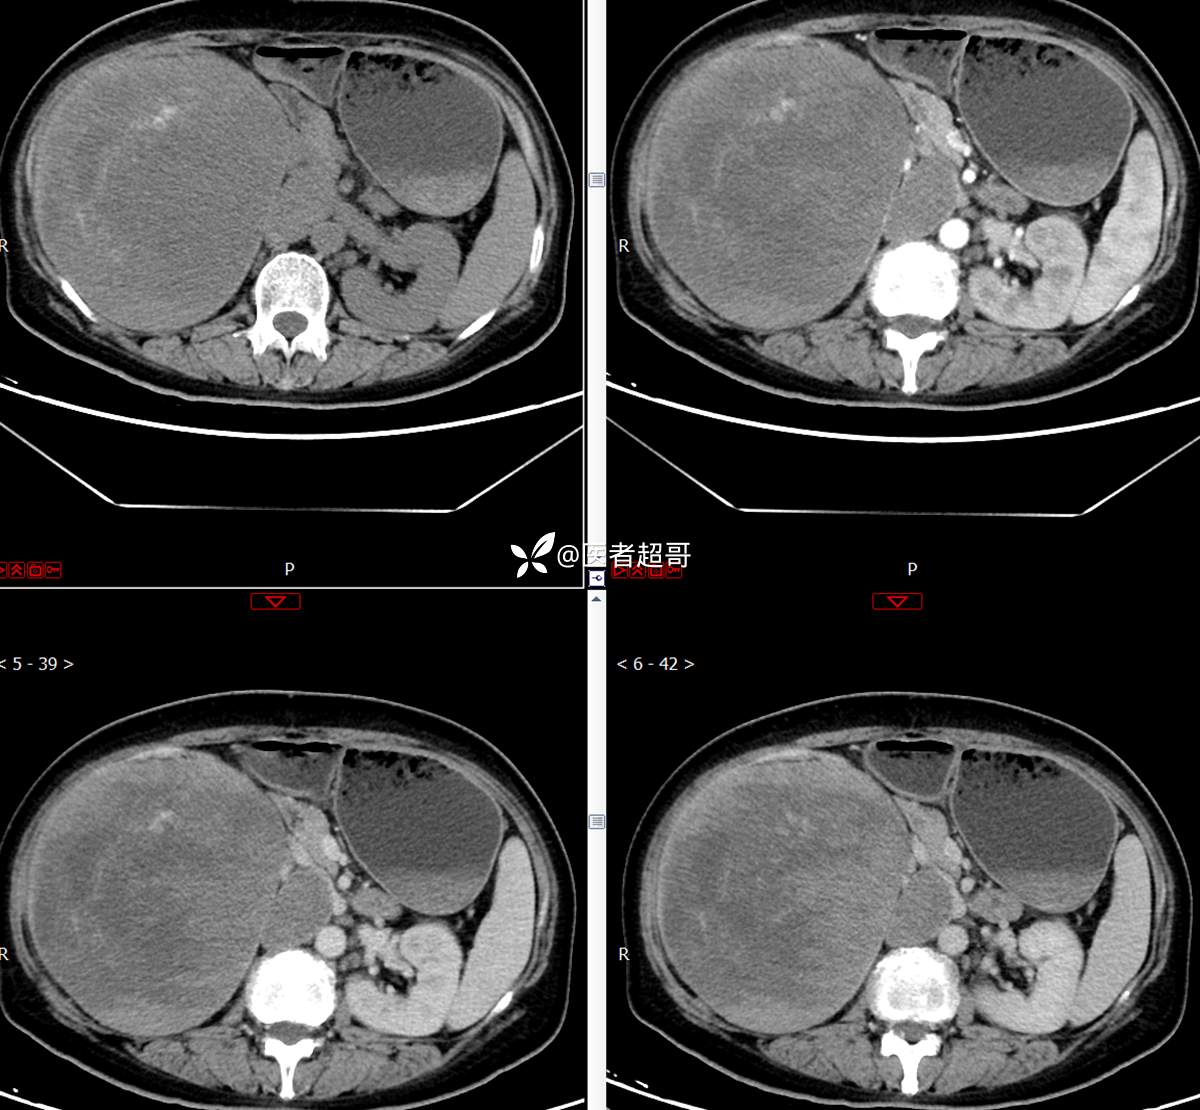

【影诊笔记743】腹腔肿物?腹膜后肿物?请先定位,后定性!有病理!

主 诉:发现右上腹肿物1周余。

现病史:患者1周余前发现右上腹有一半球形巨大肿物,约18cm*15cm大小,既往贫血病史3年余,诉乏力,易疲劳,偶有头晕,活动后心悸,无腹痛、腹胀,无恶心、呕吐,无尿频、尿急、尿痛,无排尿困难,患者为求进一步治疗,来我院消化内科就诊,门诊行肝.胆.胰.脾.肾彩超示:右肾上部囊实性占位,范围约18.0cm×11.7cm×16.4cm,边界清,形态规则,建议进一步检查,腹膜后实性结节。我科遂以“肾肿物”收治入院,患者自发病以来,神志清、精神可,睡眠、饮食可,二便正常,体重、体力略有下降。